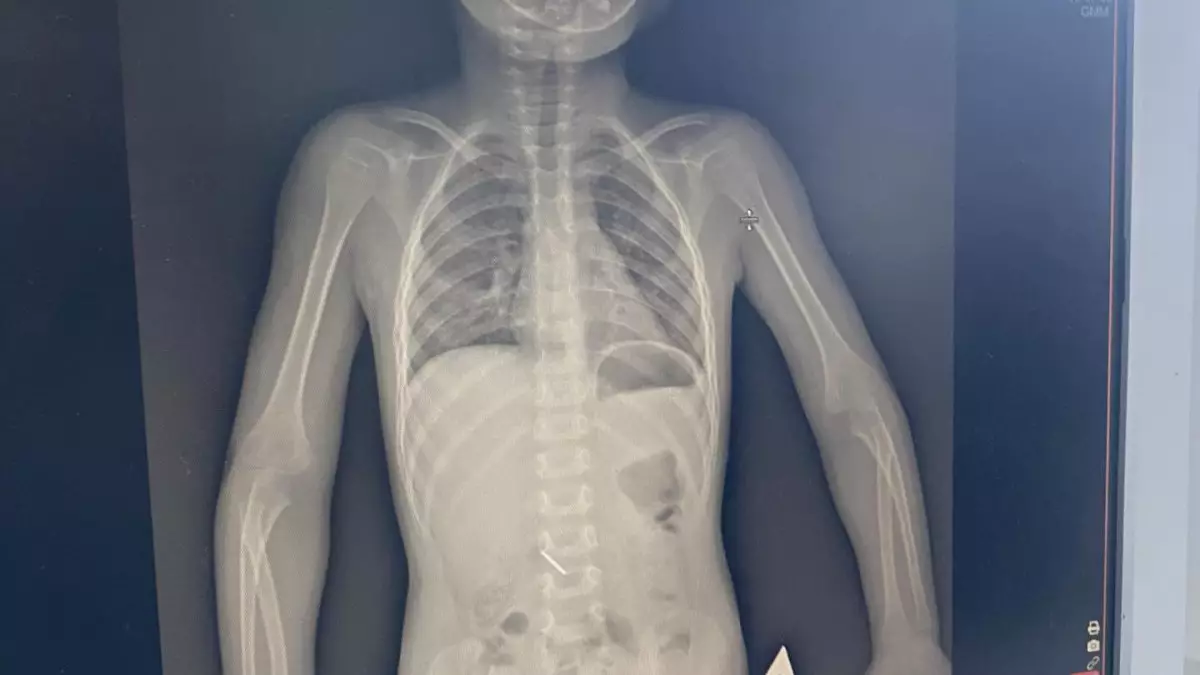

Көкшетауда стоматологияда 3 жасар қыз медициналық құралды жұтып қойды

Ештеңе етпейді, мұндай жағдайлар болып тұрады және бөгде зат өздігінен шығады деп айтқан.